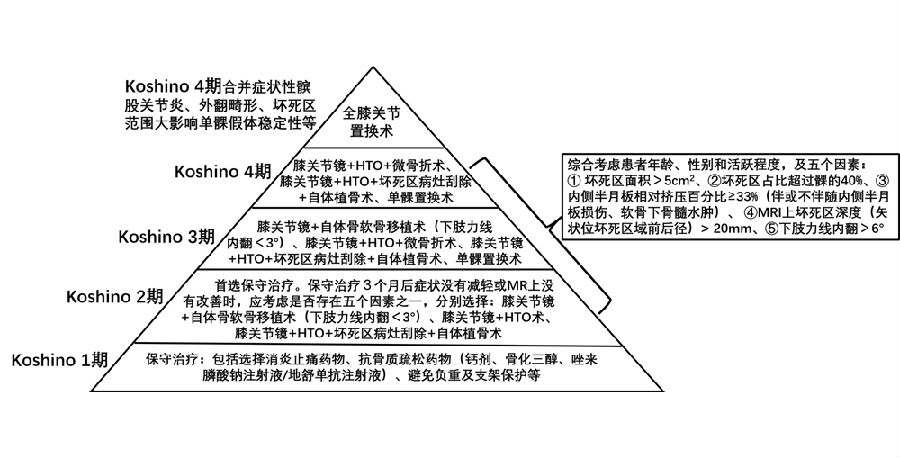

综上,影响方案选择的因素包括分期、力线、半月板损伤、影像学评估几方面。

关于影像学评估与SONK的预后的关系,多项研究表明小于3.5cm2的小坏死病变可进行保守治疗,在冠状位X片上5cm2软骨下病变面积作为预测预后不良和高风险进展的临界值,前后位X片坏死区>50%髁,会迅速塌陷,病变范围很大(>40%髁/前后位X 片)或有早期骨关节炎的影像表现,保守欠佳。

早期(3月内)内侧半月板相对挤压百分比≥33%,是SONK发病1年后预后不良的预测指标,MRI检查没有局灶性轮廓塌陷和髁深处没有低信号线(隔离带),预后好,股胫角>180°(下肢力线内翻>6°)和MRI上深度>20mm 预示SONK患者症状发作后1年预后不良。

(1)Koshino Ⅰ期 SONK

建议保守治疗,具体方案包括选择消炎止痛药物、抗骨质疏松药物(钙剂、骨化三醇、唑来膦酸钠注射液/地舒单抗注射液)、避免负重及支架保护等方法。

(2)Koshino Ⅱ期 SONK

优先选择保守治疗方案,或在保守治疗方案的基础上配合行钻孔减压术,由于Koshino Ⅱ期的关节软骨仍相对完整,借助间充质细胞的重建作用及钻孔后骨内压力的降低,在该期仍可取得满意的疗效。

如果保守治疗3个月后症状没有减轻或MR上没有改善时,患者同时存在5个因素中的任一个,则应考虑行手术治疗,选择膝关节镜+自体骨软骨移植术(当患者下肢力线内翻<3°时)、膝关节镜+HTO术、或膝关节镜+HTO+坏死区病灶刮除+自体植骨术。

(3)Koshino Ⅲ期 SONK

需在考虑5个因素的基础上,同时兼顾考虑年龄、性别和活跃程度,分别选择用膝关节镜+自体骨软骨移植术(当患者下肢力线内翻<3°时)膝关节镜+HTO术+微骨折术、膝关节镜+HTO+坏死区病灶刮除+自体植骨术或单髁置换术。

(4)Koshino Ⅳ期SONK

由于存在继发退行性改变,一般不建议单纯行膝关节镜+自体骨软骨移植术。需在考虑5个因素的基础上兼顾患者年龄、性别和活跃程度,分别选择膝关节镜+HTO术+微骨折术、膝关节镜+HTO+坏死区病灶刮除+自体植骨术或单髁置换术。对于合并症状性髌股关节炎、外翻畸形、坏死区范围大影响单髁假体稳定性等的Koshino Ⅳ期膝关节股骨内侧髁SONK,采用全膝关节置换术。

综上,膝关节股骨内侧髁自发性骨坏死的阶梯治疗应遵循下图的治疗原则。

膝关节股骨内侧髁自发性骨坏死的阶梯治疗

2、SONK的阶梯治疗中,应该重视应力源性理论,综合考虑分期、半月板损伤、半月板突出、下肢力线、坏死范围及坏死深度等因素。